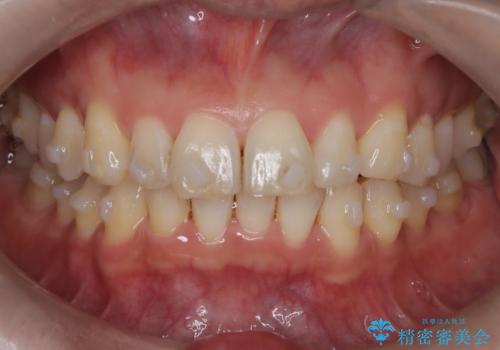

【インザライン】前歯の凸凹を治したい

- 前歯の凸凹を主訴に来院されました。

下顎位が右方に変異しており、外科矯正も提案しましたが患者様は希望されず、インビザラインにて治療を完了しております。

叢生のスペースを確保するために、臼歯部の遠心移動を行っています。

今回の治療計画は上顎の正中を顔と揃えることを優先しています。